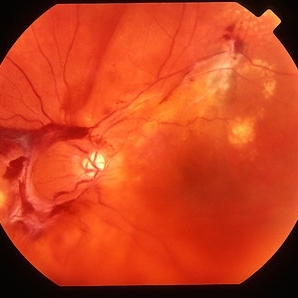

CRVO ischemic - color image

Jan 11 2013 by Alex P. Hunyor, MD

Severely ischaemic central retinal vein obstruction (CRVO), right eye - color image.

Condition/keywords: central retinal vein occlusion (CRVO), ischemic CRVO